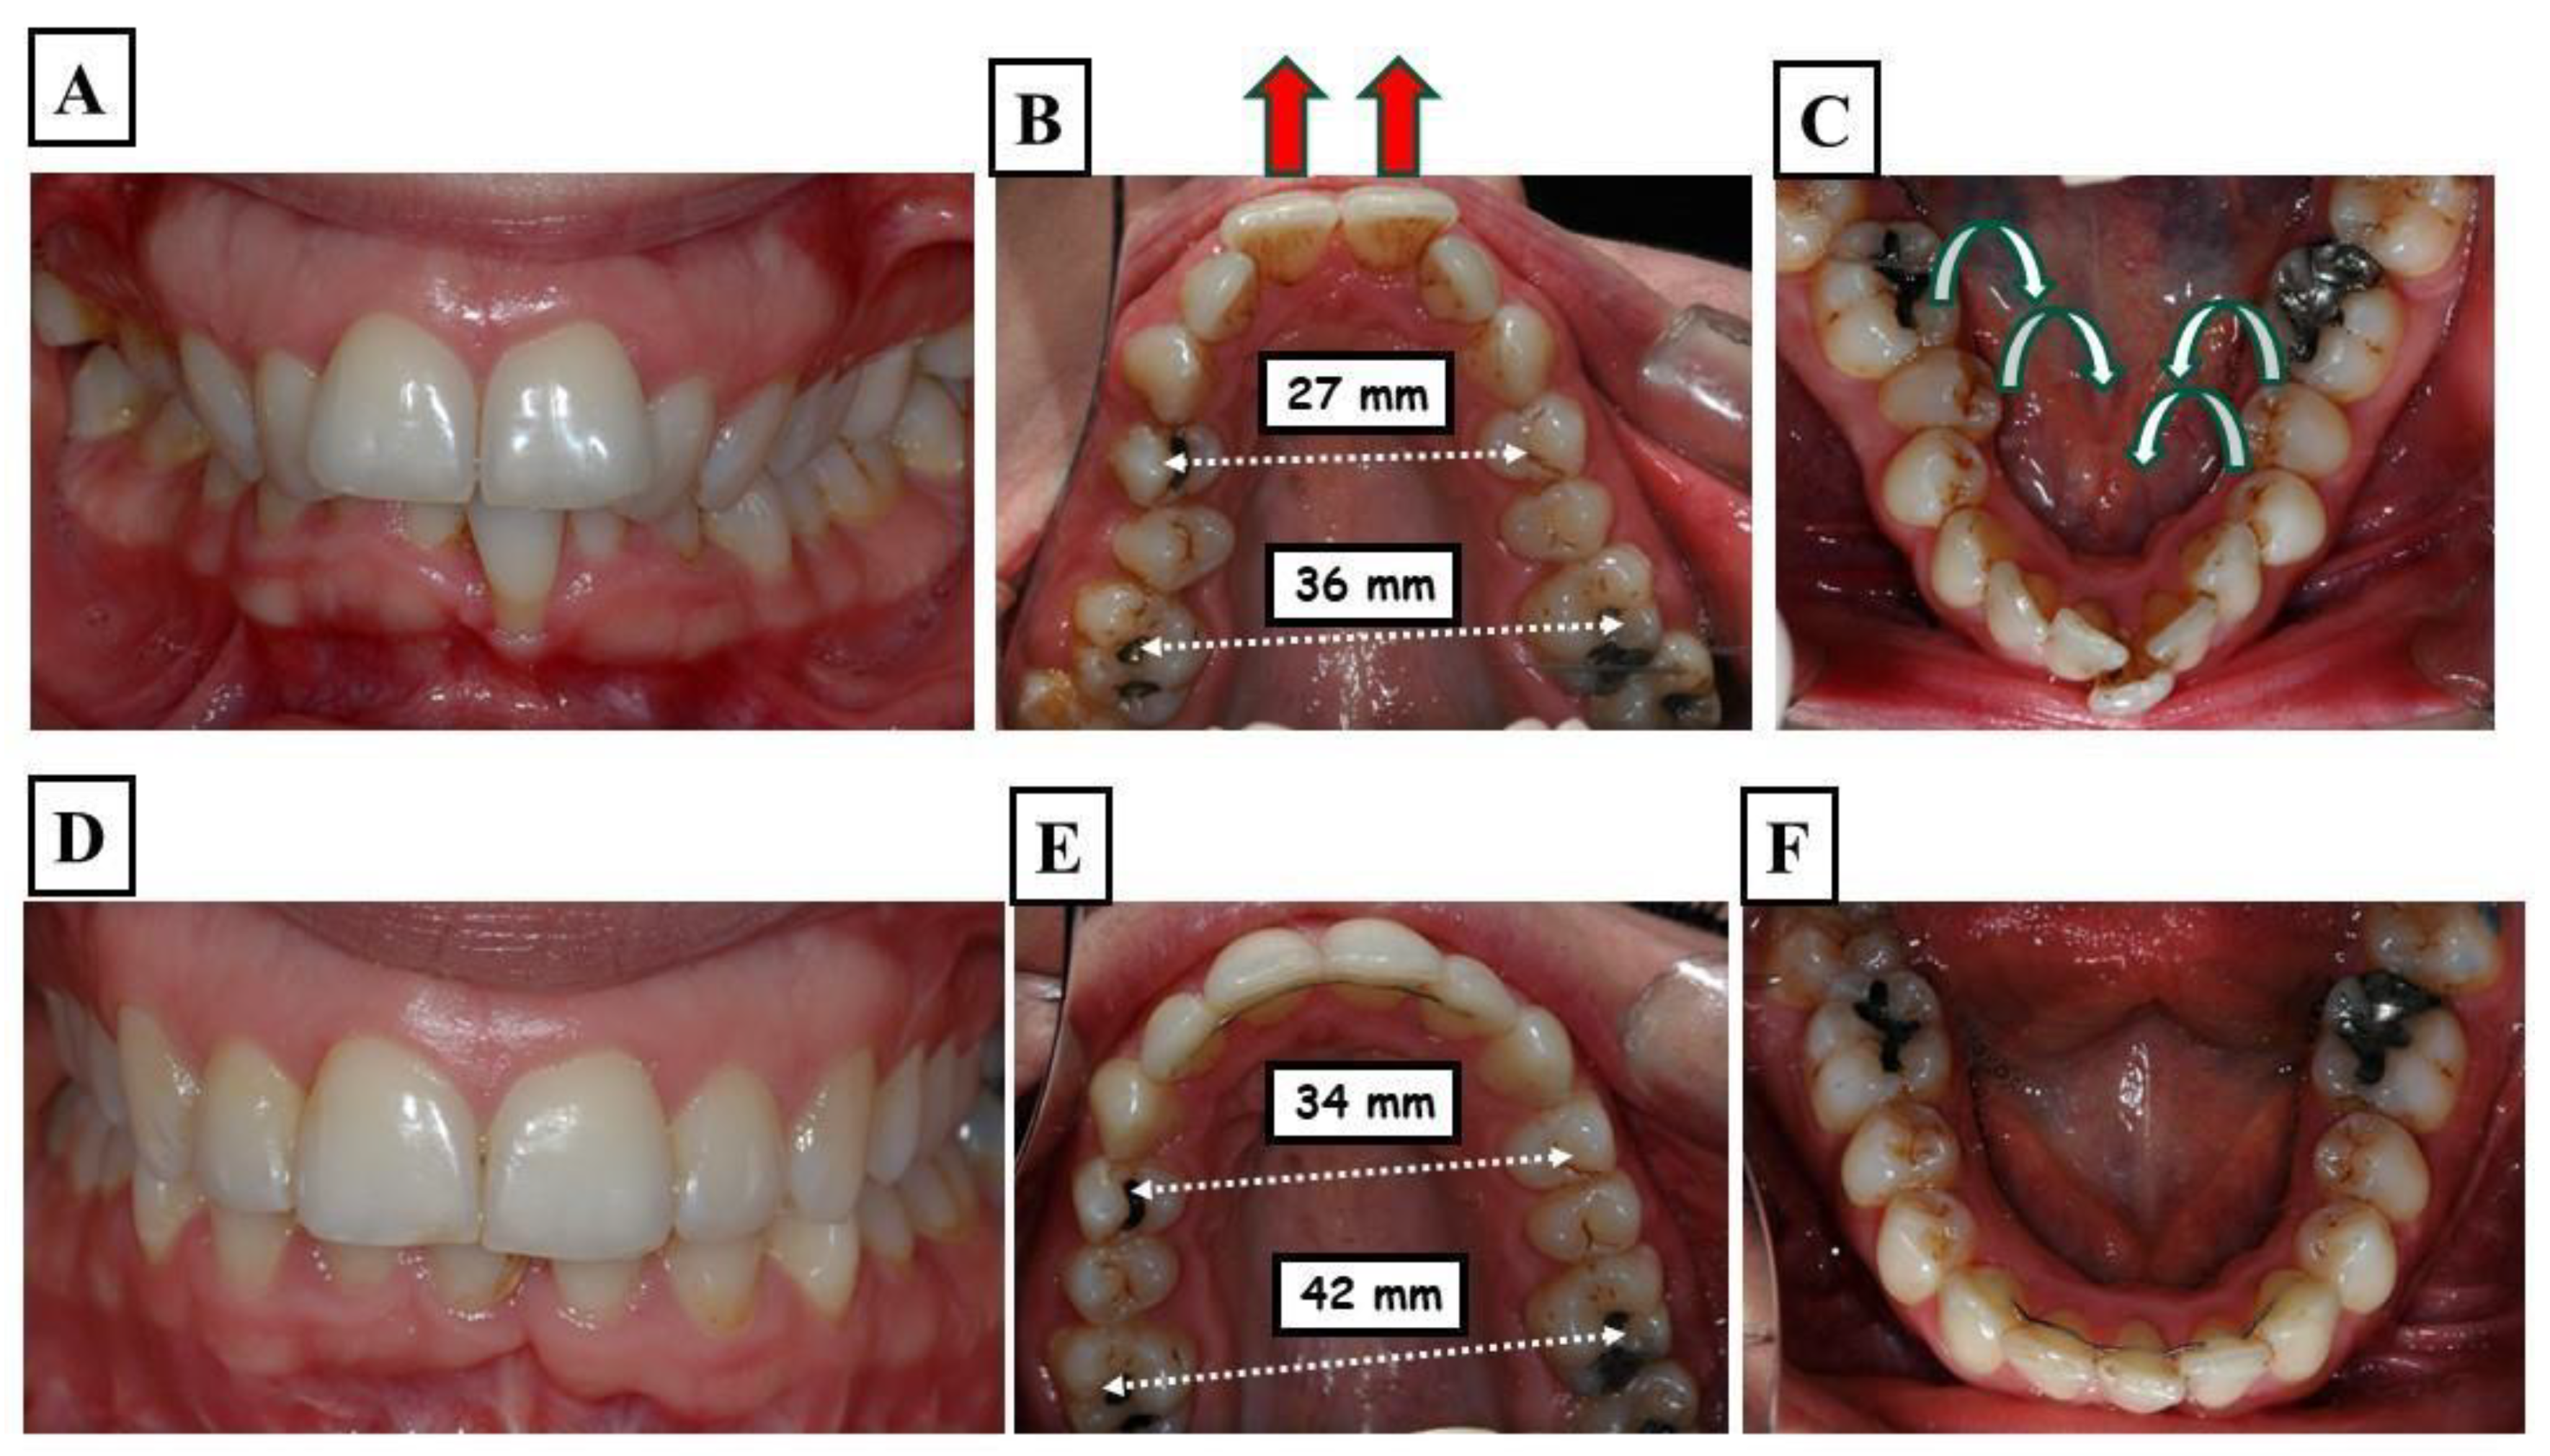

For the mandibular posterior teeth, this compensation usually entails lingual tilting, which results in an overly negatively inclined mandible. Furthermore, the maxillary posterior teeth are tipped facially. Afterward, it is said that these teeth have an overly optimistic slope (Figure 3A–F).

Figure 3.

A demonstration of a patient with a very narrow upper and lower jaw. The figure shows the situation before the start of treatment—proclination of the upper front teeth with an increased overjet (A), the upper jaw width in the molar region is 36 mm, and the molars are tilted lingually, the proclination of the upper incisors (re d arrows) caused an additional enlargement of the overjet (B), and the lower jaw has adapted to the shape of the upper jaw, showing severe crowding and lingual tilting of the molars (C). (D–F) show the situation at the end of treatment, including, stable functional occlusion, well-formed and levelled upper and lower jaws, respectively. Harmonious dental arches in all three dimensions.